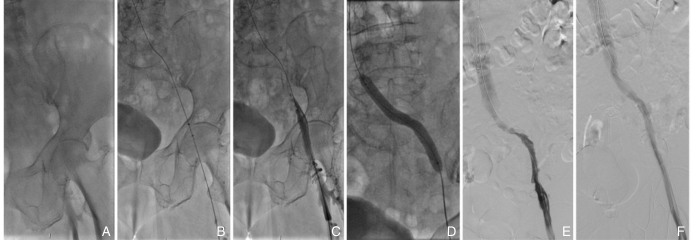

图1 FTTP治疗急性IFVT的典型术中影像 A:血栓治疗前造影图像,提示左侧IFVT,侧支形成较少;B:AngioJet导管行血栓清除术;C:AngioJet首次血栓清除术后,仍有较多血栓残留,特别是髂外静脉和股总静脉局部;D:选择AngioJet喷药模式,血栓部位喷注150 000 IU尿激酶后行球囊扩张完成机械性碎栓;E:AngioJet行第二次血栓清除后的造影图像,显示左侧髂股静脉血栓形成几乎完全清除,残余局部静脉狭窄;F:髂股静脉植入支架并球囊后扩张后最终造影,显示左侧髂股静脉通畅Fig.1 Representative intraoperative images of FTTP treatment for acute IFVT A: Preoperative venography showing left iliofemoral vein thrombosis with limited collateral circulation; B: Thrombus removal using an AngioJet catheter; C: Residual thrombus after the first thrombectomy, mainly in the external iliac and common femoral veins; D: Local spray thrombolysis with 150 000 IU of urokinase followed by balloon-mediated thrombus fragmentation; E: Venography after the second thrombectomy showing near-complete thrombus clearance; F: Final venography after iliac vein stent implantation and balloon post-dilation demonstrating restored venous patency